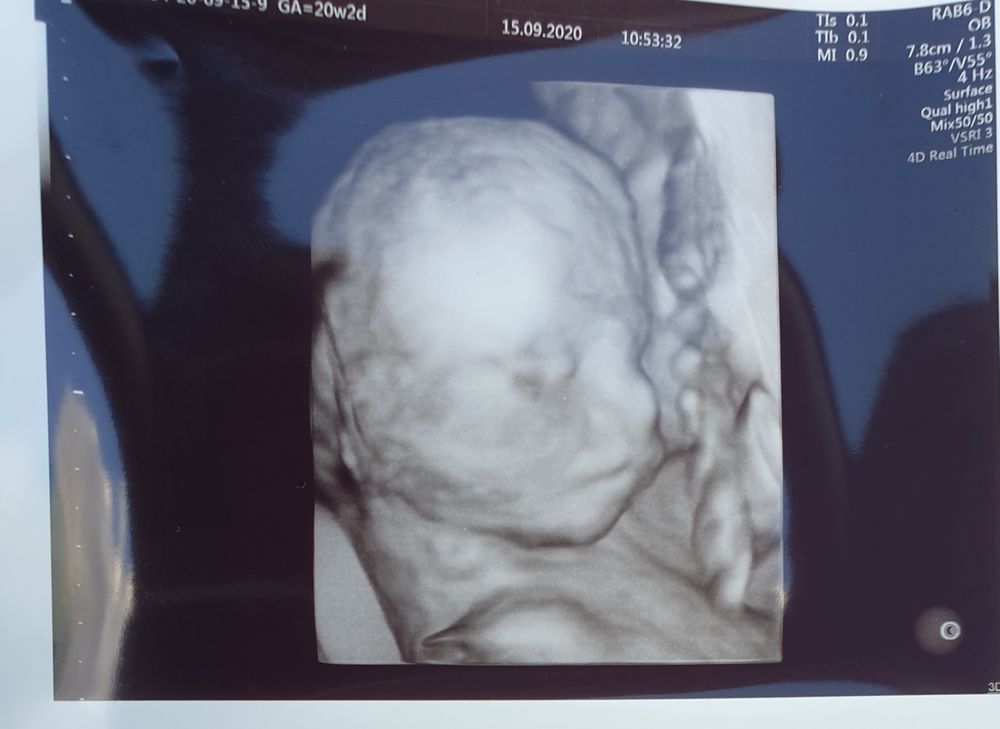

Лучше всего личико видно, когда ещё много околоплодных вод, 21-23 недели должно быть ещё норм. Я не помню, на каком сроке прошлый раз была, но вот в 31 неделю уже толком не посмотришь, т.к. тесновато, у него то ручки перед лицом, то пуповина, то в матку упёрся мордашкой

Почти 31 неделька и 21 неделька